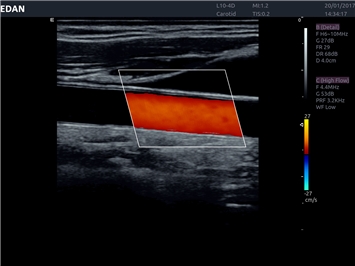

• Автоматическое измерение толщины интима-медиа

• Сосудистой диагностики

Цветовой допплер:

Да